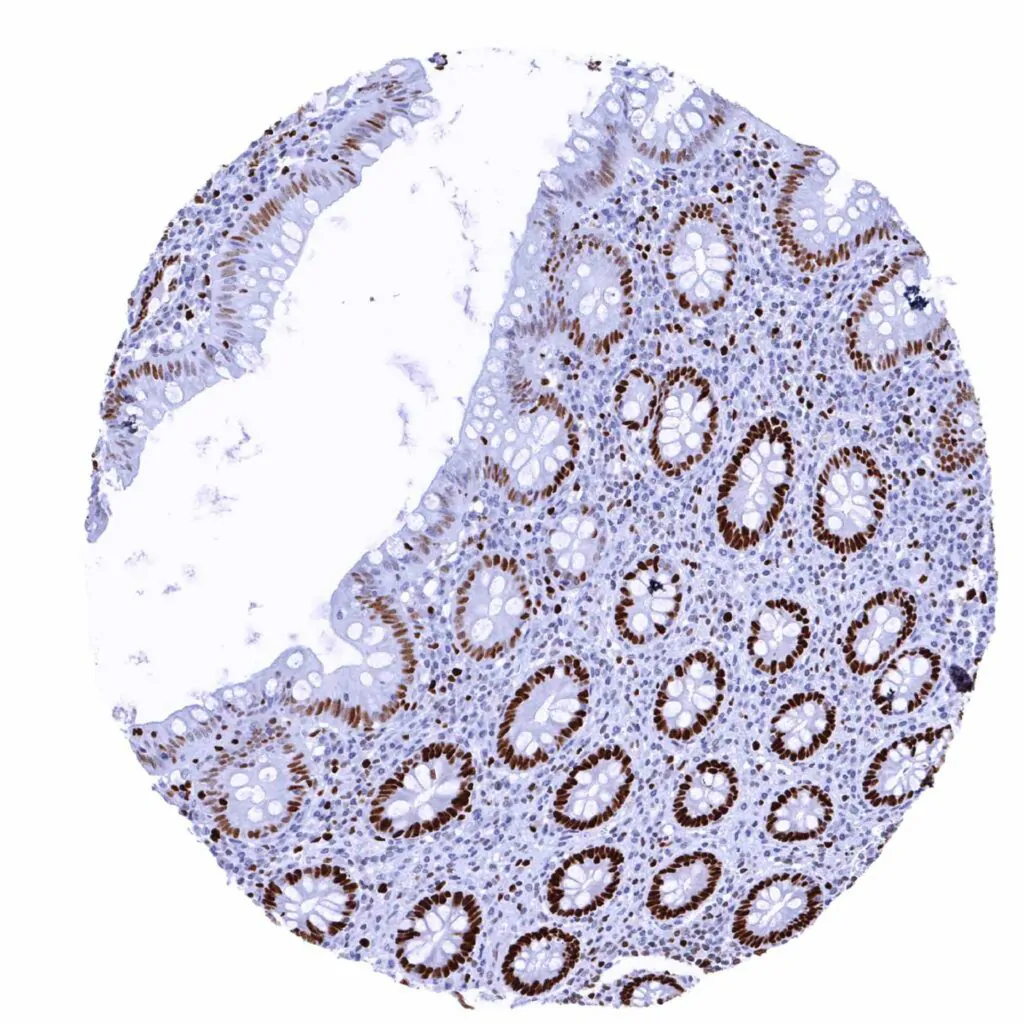

Appendix, mucosa – MCM2 staining predominates in in epithelial cells of the crypts. Some lymphocytes are also positive